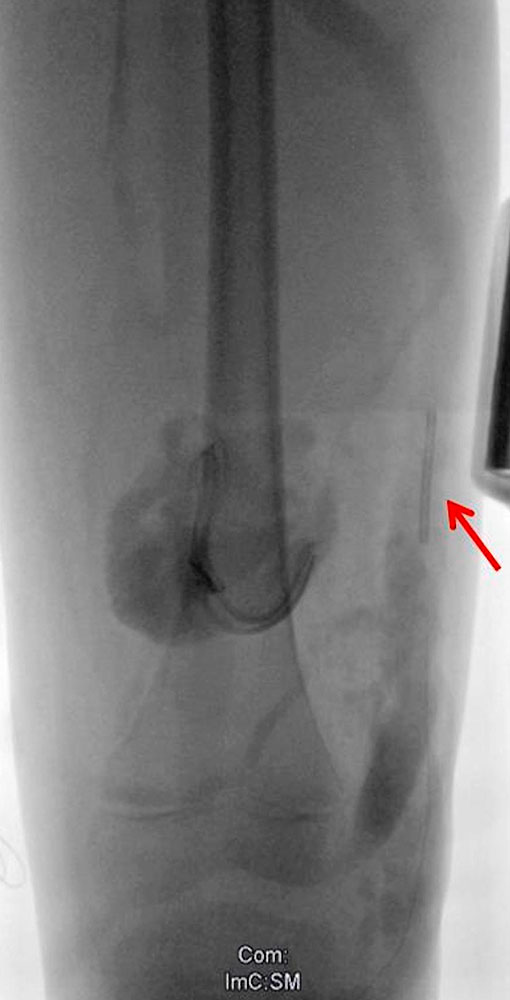

Embolization of communicating veins

The catheter-assisted insertion of thrombogenic materials such as coils, glue and plugs is a possible option in the therapy of large-lumen and deep venous malformations. The main purpose of this method is to close large veins communicating with the deep vein system.

Although this does not “dry out” the entire malformation, it can be useful to close the communication of a particularly large-lumen part of it with the deep venous system. Subsequent sclerotherapy can then be carried out effectively and without complications, without the sclerosing agent being able to drain off. The embolization is intended to reduce the blood volume of the affected body part and thus the associated, troublesome tightness. However, the radiologically detectable success of the intervention is not always reflected in the clinical outcome.

After successful embolization, the symptoms can be very varied: improved, unchanged or even worse. The value of embolization should not be diminished by this statement. Instead it means that experience with the indication still needs to be gathered.

With very few exceptions, transarterial catheter embolization to occlude arteriovenous fistulas into the venous malformation is not indicated and should be avoided.